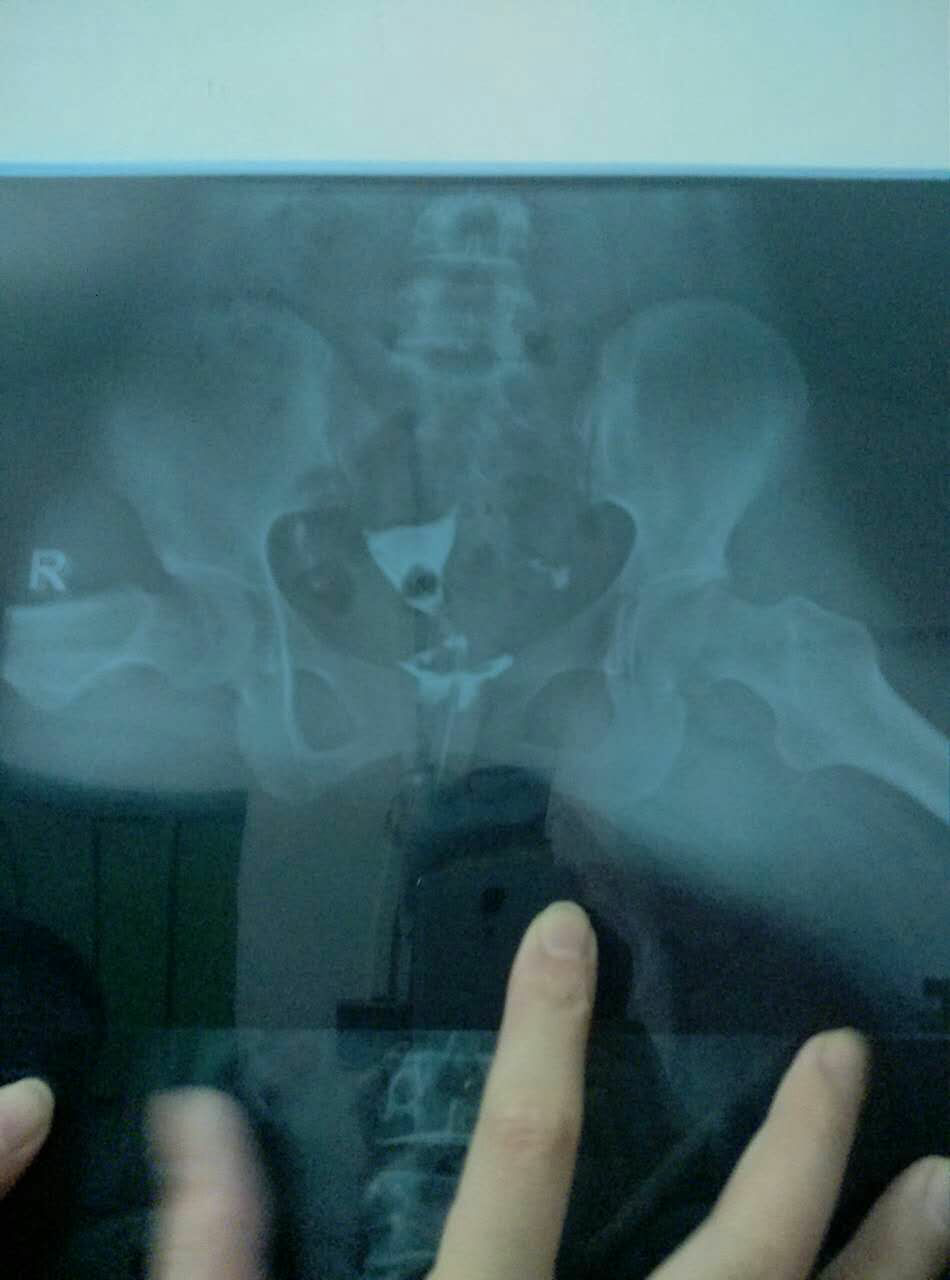

输卵管造影结果,请各位医生帮忙看看 有什么治疗方法?谢谢!

今天做的输卵管造影,请各位医生说说我该怎么治疗。